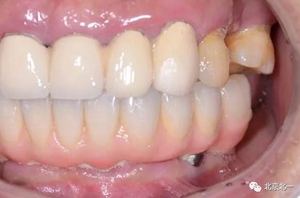

圖二十五:口內(nèi)照。